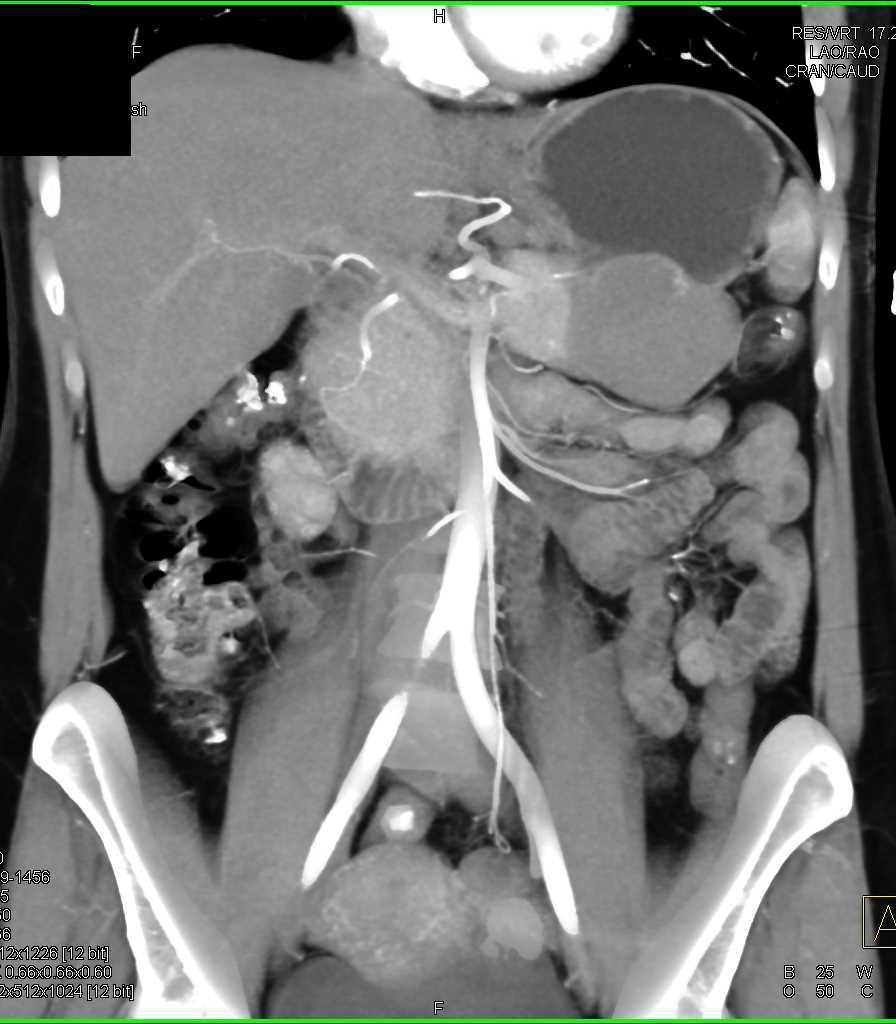

Mass Pushes on Tail of Pancreas was Ganglioneuroma